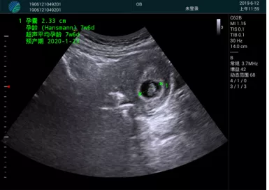

病例一:

清晰顯示孕囊,通過軟件包計(jì)算孕齡7w+6d

M20實(shí)時(shí)引導(dǎo),術(shù)中清晰顯示孕囊被破壞和抽吸針的過程,清晰顯示吸引針

抽吸結(jié)束后縱切子宮,孕囊已被完全抽吸,未見明顯殘留

橫切子宮,發(fā)現(xiàn)右側(cè)宮腔靠近宮角處有少許脫模樣殘留

M20引導(dǎo)下,抽吸針找到右側(cè)宮角處再次清掃

二次抽吸后再次進(jìn)行超聲檢查,宮腔未見殘留,宮腔線清晰顯示